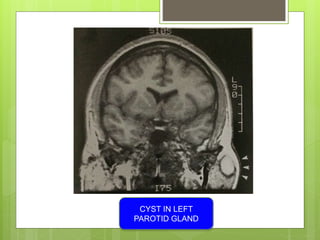

CYST IN LEFT

PAROTID GLAND